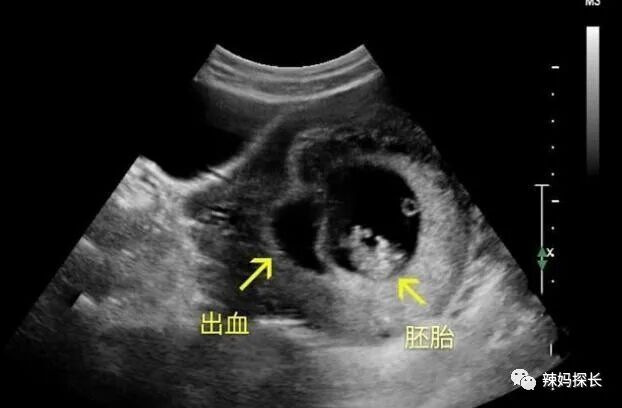

突然的“见红”

见红这就是流产比较明显的信号了,如果说怀孕了,但是突然出现了见红的情况,一定要赶紧去医院进行检查,因为孕期见红不是正常反应。

●如果只是轻微的先兆流产还是可以保胎处理的

●如果说孕妇自己都没有重视,错过了最佳的时间,导致胚胎已经停止发育了的话,那就没办法挽救了。